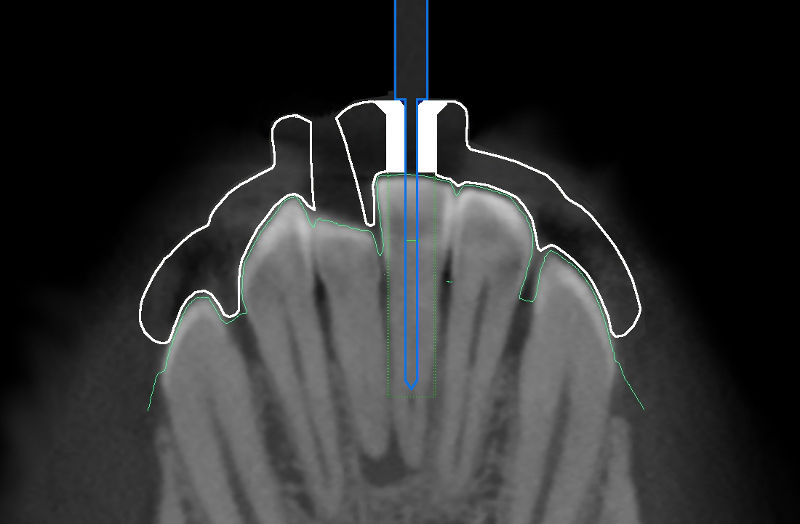

Endodontie durch die Bohrschablone, coDiagnostiX™

Eine auf den Bohrer abgestimmte Bohrhülse wird in die geplante Bohrschablone eingefügt, so dass auch eine

Tiefenkontrolle möglich ist. Die Geometrie der Bohrschablone wird exportiert und kann entweder gefräst oder gedruckt

werden. In die Bohrschablone wird die Bohrhülse aus Titan eingesetzt und führt den Bohrer entlang der zuvor bestimmten

Achse, so dass der Kanal wie geplant aufbereitet werden kann.